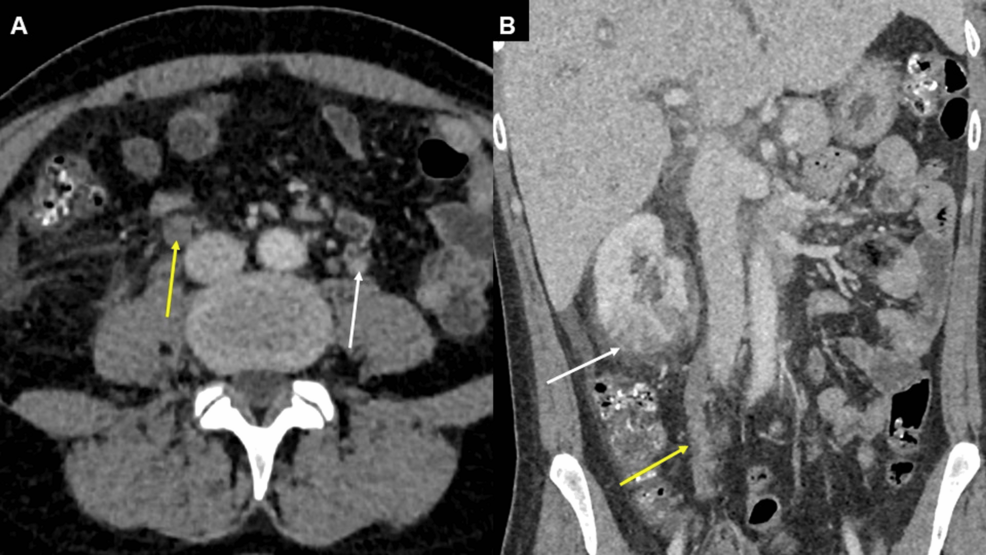

- Who’s at risk? Women with postpartum infections, C-sections, or a history of blood clots. If you’ve had a fever for more than 48 hours after delivery, demand a CT scan—don’t assume it’s “just a UTI.”

- Diagnostic certainty: CT or MRI venography is the gold standard, but access varies. A 2025 American Journal of Obstetrics & Gynecology study (N=892) found that 38% of U.S. Hospitals lack 24/7 radiology support for postpartum imaging.